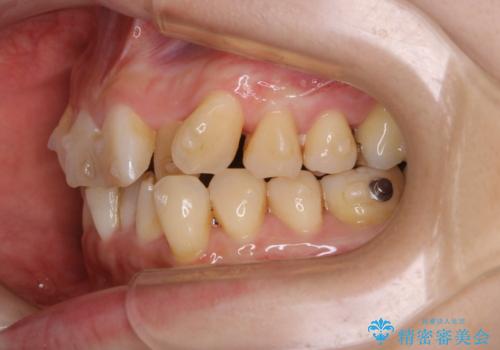

- インビザラインでのマウスピース矯正中に、歯の黄ばみが気になるため綺麗に白くしたいとのことでした。PMTC60分コースを行いました。

PMTC(保険外治療)は、毎日の歯磨きで落としきれない汚れや、コーヒ、紅茶・タバコのヤニなどの着色も除去します。目には見えない歯と歯の間・歯肉の境目・インビザライン中はアタッチメント周囲などに残っているプラーク(歯垢)もしっかり取り除きます。PMTCでは専門的な機械や材料を使用して、徹底的に汚れを除去するため、虫歯・歯周病・口臭予防などにつながります。